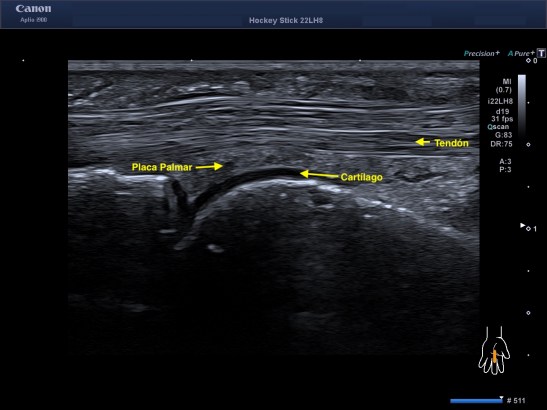

3. Tendón: Son bandas de tejido conectivo muy resistentes que se sitúan a cada extremo del músculo y que lo sujetan al hueso. Tiene una estructura de fibras muy marcadas fruto de la diferencia de ecogenicidad entre colágeno y endotendón que es hiperecogénica y el paratendón que es hipoecogénico.

Hay que eliminar la idea de que el tendón es solo una estructura fibrosa que une hueso y tendón, también hay tendones intramusculares. También

9. Cartílago: Es un tipo de tejido conectivo especializado, elástico, carente de vasos sanguíneos compuesto de colágeno tipo dos y de proteoglicanos llenos de agua y por eso es hipoecogénico.